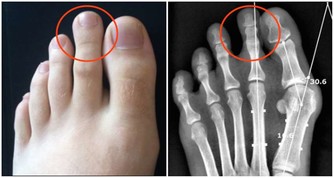

腿部抽筋

夜間腿部肌肉痙攣?疼到不能行?

其實,這是因為身體津液太低,濡養不好肌肉、筋造成的。夏天出汗多,本身就在傷津液,所以容易出現。

建議:睡前做拉伸運動、洗個熱水澡和喝碗熱粥等。經常出現抽筋的問題,可考慮經方——芍藥甘草湯。